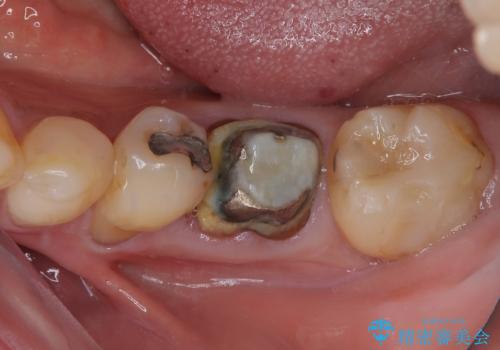

最新の症例

Latest cases